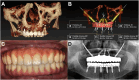

Dynamic navigation technology combined with zygomatic implants as a surgical strategy for insufficient maxillary bone volume

Keywords: All-on-X; Dental implant; Dynamic navigation; Maxillary bone; X-Guide; Zygomatic implants.